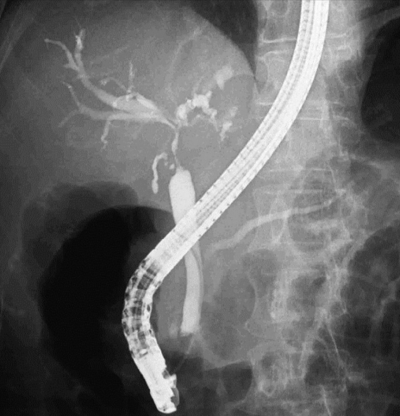

血液所見:赤血球 432 万、白血球 7,600、血小板 26 万。血液生化学所見:総ビリルビン 7.9 mg/dL、直接ビリルビン 5.2 mg/dL、AST 271 U/L、ALT 283 U/L、ALP 2,118 U/L(基準 115〜359)、γ-GTP 605 U/L(基準8〜50)、アミラーゼ 42 U/L(基準 37〜160)。CRP 6.1 mg/dL。ERCPを示す。

最も可能性が高いのはどれか。

e. 胆管癌